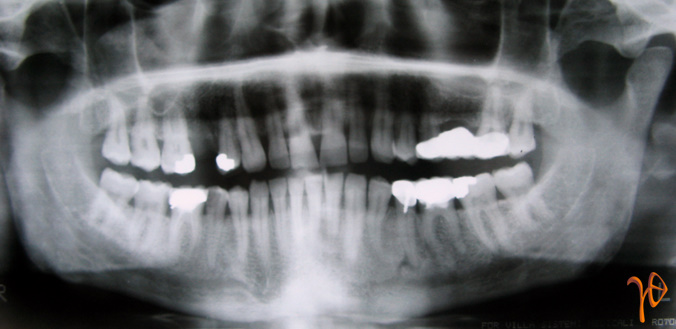

Στην πανοραμική ακτινογραφία δεν προέκυψαν ευρήματα από το οστούν της άνω γνάθου(Εικ.1). Στην απλή ακτινογραφία των ιγμορείων διαγνώστηκε συλλογή στο σύστοιχο ιγμόρειο(Εικ.2).

Εικόνα 1. Πανοραμική ακτινογραφία χωρίς ευρήματα.